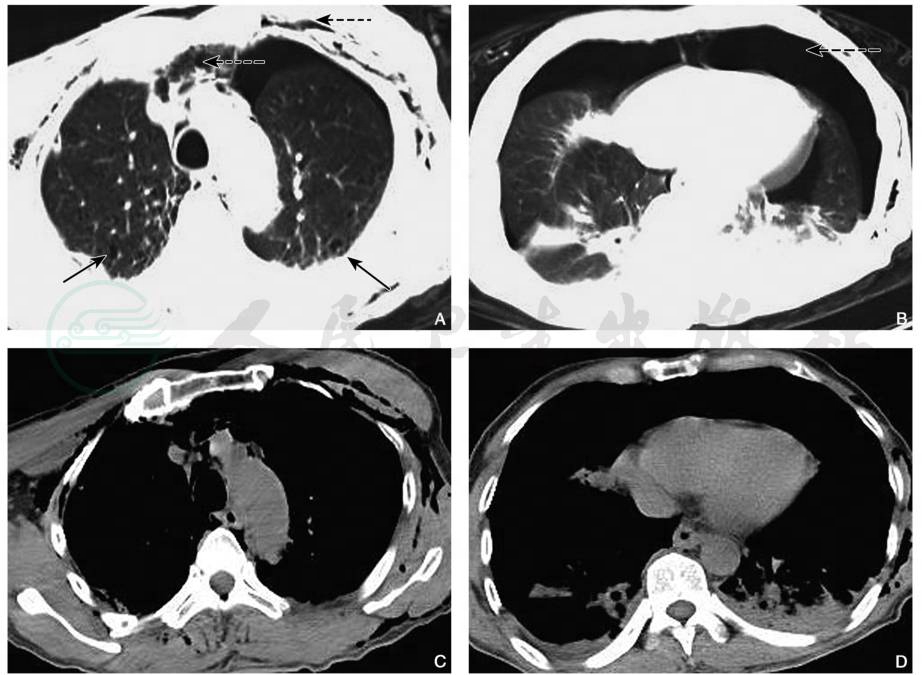

3.复合性挫裂伤

复合性挫裂伤是指既有肺撕裂的CT表现,又合并有轻重不一的胸腔积液、气胸、血气胸、纵隔气肿或皮下气肿,及相邻肋骨、胸骨或其他胸背部骨折的多发性损伤表现(图7、图8)。

图7双肺复合性挫裂伤

男性,56岁,胸部CT平扫肺窗(A、B)显示双肺膨胀不良,双肺野内见片状及絮状高密度影,边界模糊;双肺内另见囊状透亮影(实箭),胸壁、胸腔、纵隔内见气体密度影(虚箭),纵隔窗(C、D)显示双侧胸腔积液

引自:中华影像医学·呼吸系统卷.第3版.ISBN:978-7-117-28903-0.主编:

图8肺血肿及肺气囊

男性,23岁,胸部CT平扫肺窗(A)显示左肺下叶团块状高密度影(实箭),周围见挫伤肺组织,同时可见外伤性肺气囊(虚箭);同层纵隔窗(B)显示左肺下叶软组织及稍高密度影